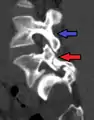

- Anterolisthesis L5/S1. Blue arrow normal pars interarticularis. Red arrow is a break in pars interarticularis.